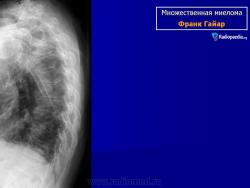

Рентгенологические проявления миеломы бывают классическими с четкими литическими очагами, окруженными ободком склероза, также характерен остеопороз различной степени выраженности, что часто приводит к патологическим переломам. В 25% случаев очаг поражения не выявляется при обычной рентгенографии, при помощи КТ и МРТ выявляют маленькие очаги поражения.

МИЕЛОМА, МНОЖЕСТВЕННАЯ МИЕЛОМА, МИЕЛОМНАЯ БОЛЕЗНЬ, СЕКРЕТИРУЮЩАЯ ЛИМФОМА, ПЛАЗМАЦИТОМА, БОЛЕЗНЬ РУСТИЦКОГО и т.д. – все это синонимы одного заболевания, которое обусловлено неконтролируемым ростом плазматических клеток, продуцируемым костным мозгом. Плазматические клетки, в свою очередь, являются конечной стадией дифференциации В-лимфоцитов – основного звена клеточно-гуморального иммунитета, основная функция которых – продукция иммунных белков – иммуноглобулинов IgG, IgA, IgM, IgE, IgD, участвующих в гуморальном иммунитете. Поэтому в норме костный мозг всегда содержит некоторое количество плазматических клеток. Однако, в случае их неконтролируемого роста увеличение количества плазматических клеток приводит к их сосредоточению в виде плазмацитомы в костном мозге, особенно в позвоночном столбе, тазовых костях, ребрах, плоских костях черепа, головках тазобедренных суставов, в результате чего нормальная костная ткань и костный мозг разрушаются. Очаги деструкции видны при рентгеновском исследовании, но, к сожалению, разрешающая способность рентгена позволяет выявить разрежение костной ткани, если порядка 30% ее уже разрушено. Миеломные клетки продуцируют иммуноглобулин одного вида (моноклональный), который при специфическом электрофоретическом исследовании сыворотки крови и мочи проявляется пиком, называемым М-градиентом, где М - означает моноклональный или миеломный. Отсюда происходит название болезни – миелома. Моноклональные белки (протеины), продуцируемые миеломными клетками, имеют измененную структуру, не выполняют функций иммунитета и называются «парапротеинами». Иногда они теряют какую-то свою часть и могут продуцироваться только моноклональные легкие цепи (белок Бенс-Джонса), или моноклональные тяжелые цепи.